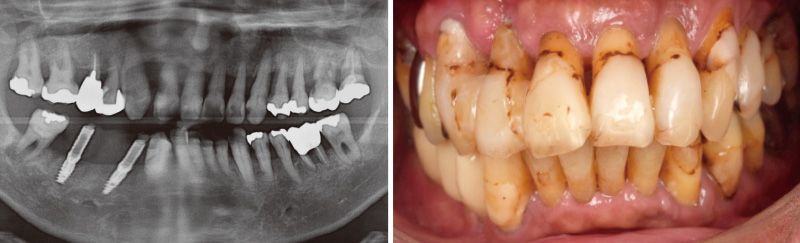

初診時より、歯周病の進行や根面う蝕が認められましたが、本人が治療を望まず、介入ができませんでした。しかし、2019年に歯周病が進行したことで本人もいよいよ自覚され、治療を承諾。₄, ₆に即時荷重によるインプラント埋入を行いました。この治療をきっかけに本人の覚悟が決まり、全顎的な治療に進むことができました。

![[写真] 2019年に₄ , ₆にインプラントを埋入](/academic/dentalmagazine/wp-content/uploads/sites/2/2026/04//196-12_photo01.jpg)

症例1-1 2019年に₄, ₆にインプラントを埋入 -